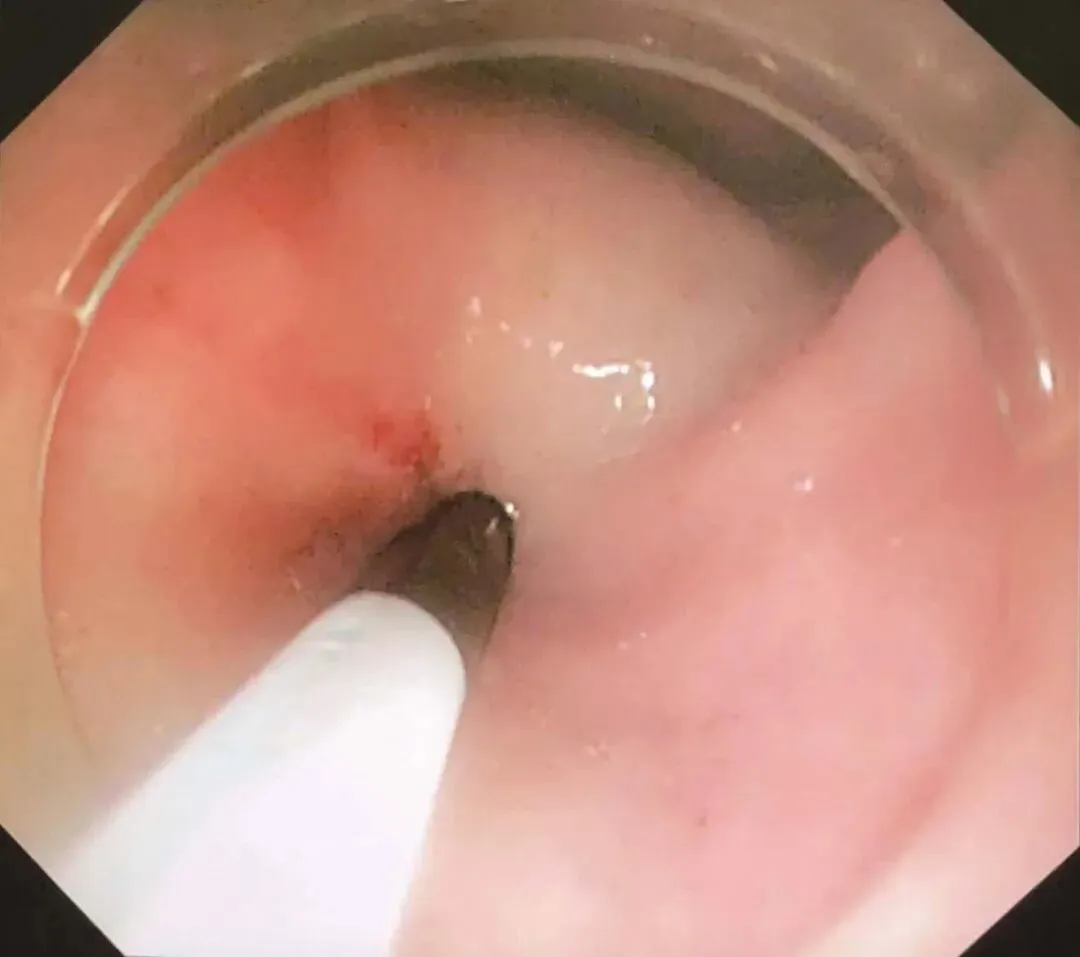

患者于2018年08月30日在笔者单位接受“腹腔镜+胃镜双镜联合胃肿瘤切除术”,胃肠外科与消化科医师共同上台。术中内镜见胃体小弯侧后壁直径4cm黏膜下肿瘤,腔内生长,未侵犯胃黏膜及浆膜(图2-3),胃周淋巴结无肿大,小网膜囊内可及直径1cm钙化脂肪结节一枚,肝脏、盆腔、腹膜未及转移灶。经口置入内镜,探查肿瘤,于肿瘤边缘黏膜下注水(图2-4);内镜指引下,腹腔镜下以超声刀距肿瘤边缘1cm切开胃壁浆膜,沿肿瘤包膜外,全层切开胃壁,完整切除肿瘤(图2-5);以3-0可吸收线间断全层缝合胃壁缺损;术中胃镜检查胃创面;创面部分黏膜缺损处内镜下以钛夹封闭(图2-6);肿瘤标本置于标本袋内,经脐部戳孔处取出(图2-7)

图2-3 术中内镜探查肿瘤

图2-4 术中内镜下于肿瘤边缘黏膜下注水